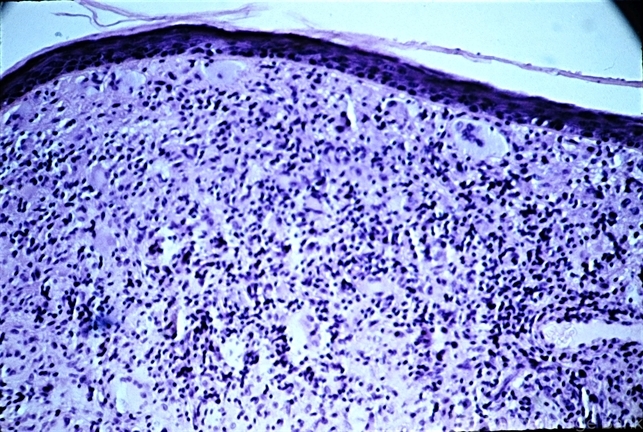

- macrophage accumulation, epidermis, giant cell

- Bland, foamy macrophage accumulation in the dermis from xanthelasma. Note the single Touton giant cell below the center.